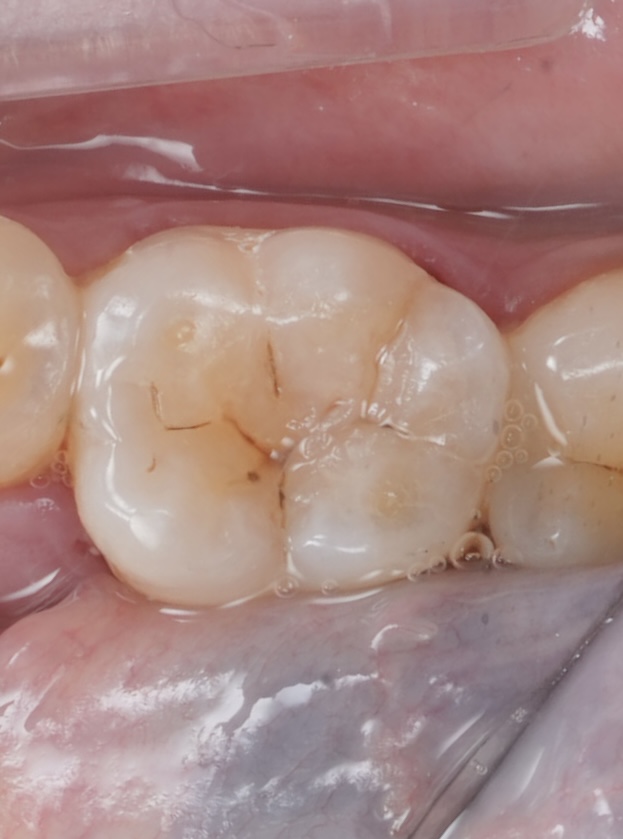

Using a fine brush and thin spatula, cusp inclinations and secondary grooves were sculpted pre-cure, replicating natural occlusal morphology. The final increment was light-cured for 40 s per surface under glycerin gel to eliminate the oxygen-inhibition layer (Fig 4).

- Fig 4: Anatomical sculpting before final curing.